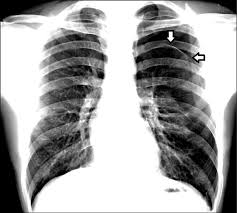

肺的表面包有一層膜,稱之為臟層胸膜,胸壁內層也有一層膜,稱之為壁層胸膜,兩層胸膜之間的間隙稱為胸膜腔。

正常情況下,這個密閉胸膜腔裡面的壓力是低於大氣壓的,這樣不僅可以使肺處於擴張狀態,也能促進靜脈血和淋巴液的迴流。

而當胸部創傷累及胸壁、肺或氣管時,空氣會經創口進入胸膜腔,導致腔內積氣,這就是常說的氣胸,會影響肺擴張。